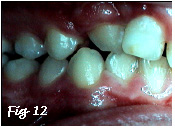

Les malpositions dentaires diverses que l'on rencontre en denture lactéale, même si elles peuvent être sévères - ce qui n'est pas le cas sur laphoto ci-dessous,

Fig.1

ne sont en principe pas corrigées car le caractère transitoire de ce stade de la dentition rend tout traitement inop-portun. Nous voulons éviter de solliciter trop tôt la coopération du jeune enfant en lui imposant un appareillage qui n'est, le plus souvent, pas indispensable.